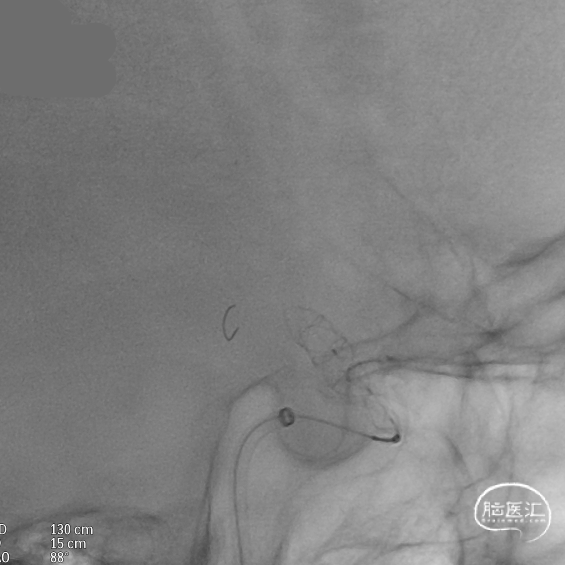

输送导丝及微导管回撤:释放至支架末端,减张系统,回撤支架导管,释放支架。沿支架推送杆,调节系统张力,将支架导管通过支架到达C7段。

支架内使用成襻微导丝进行按摩,使支架充分贴壁。